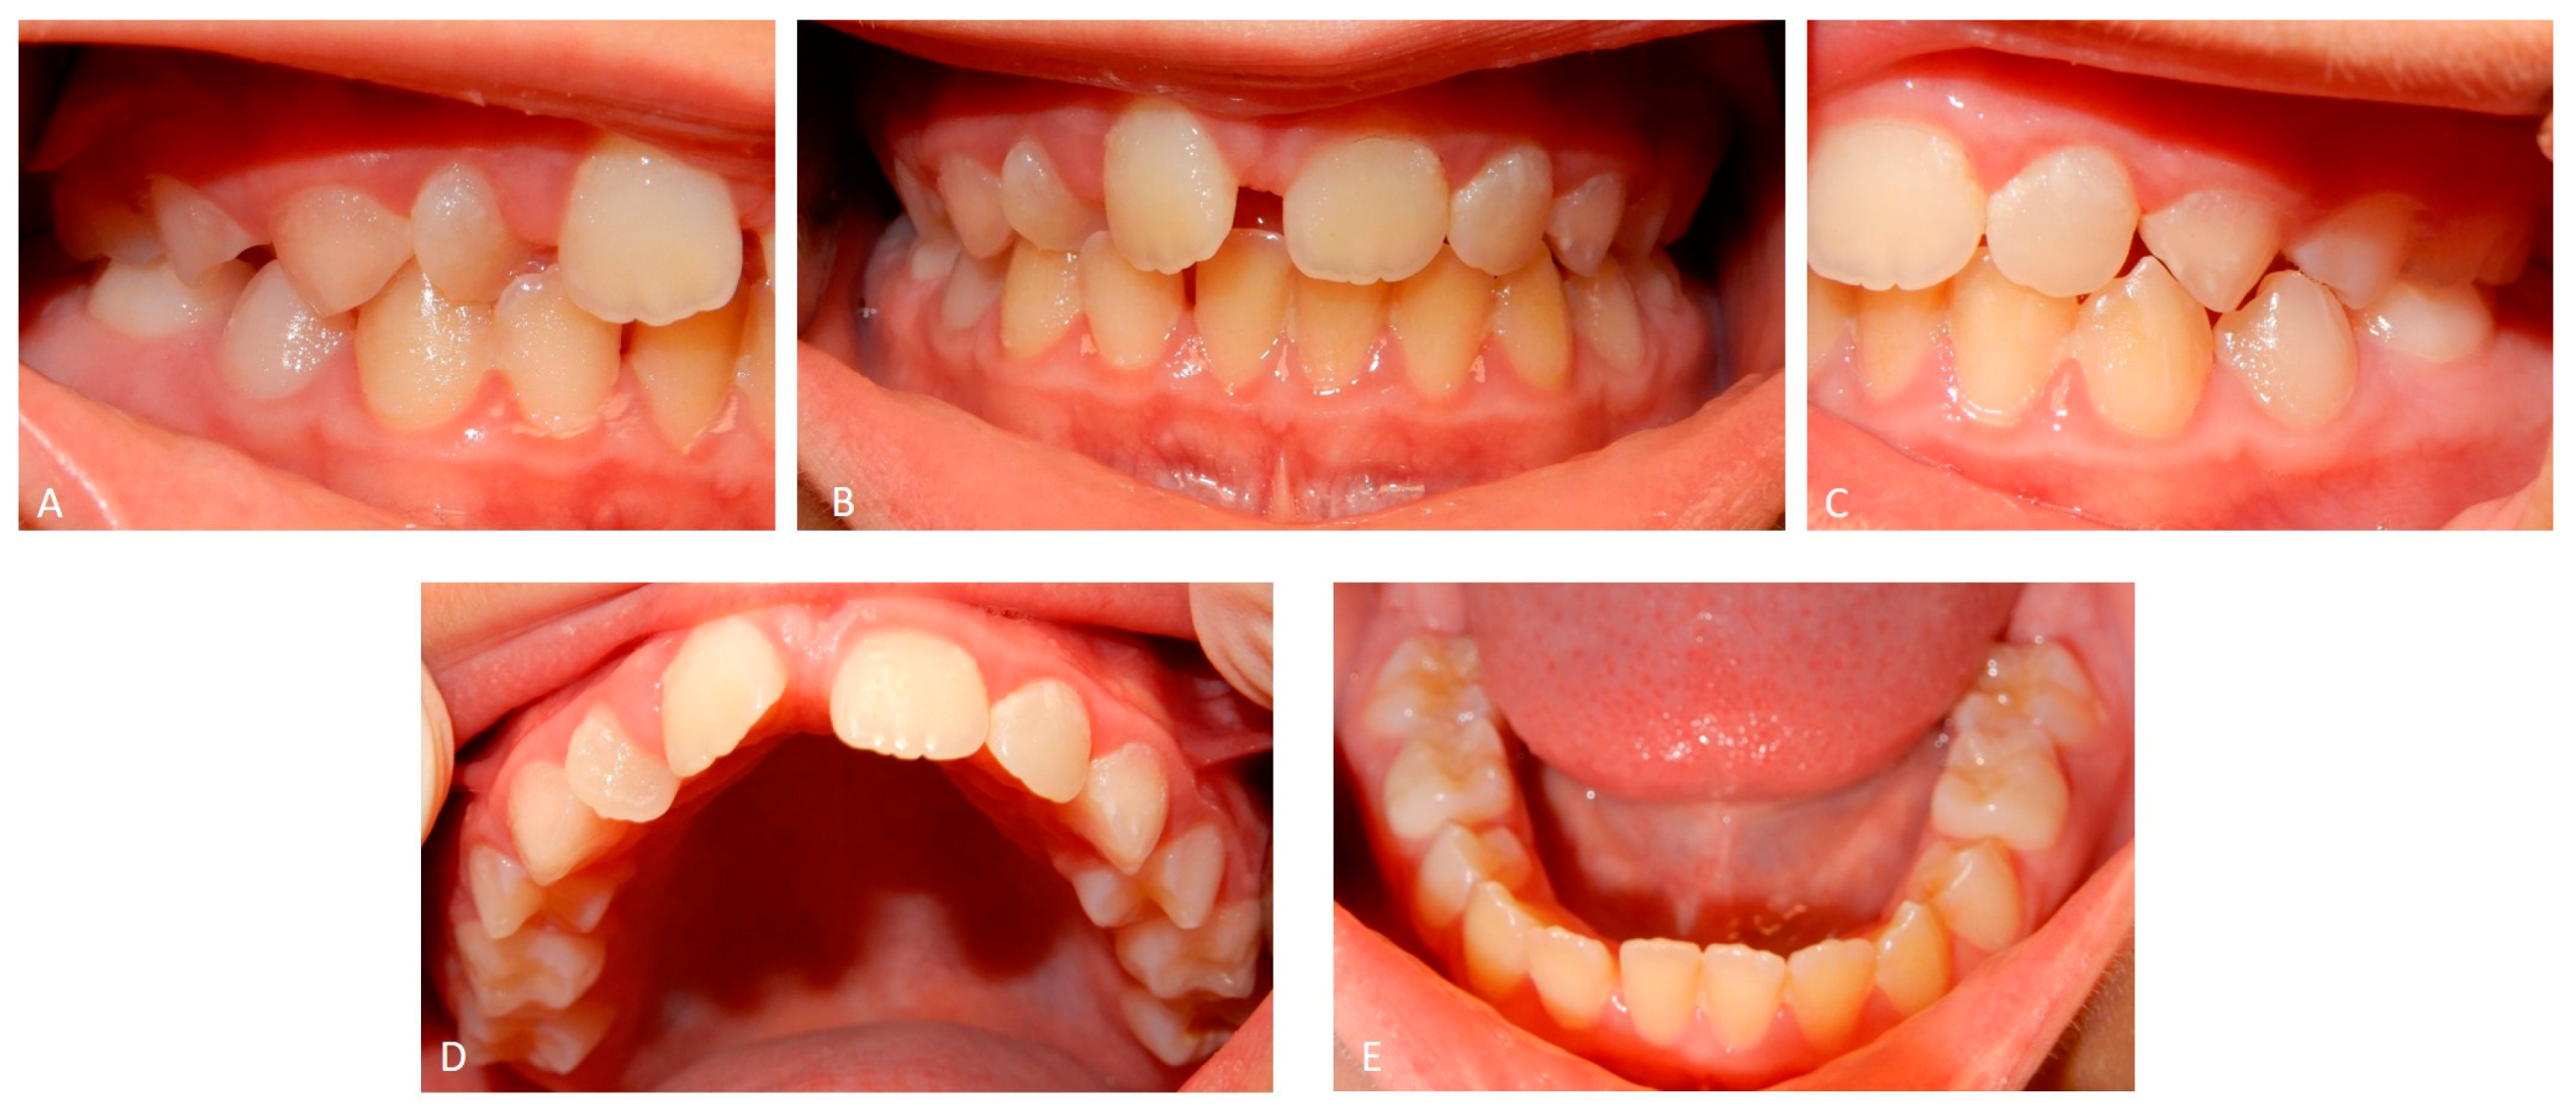

2.1. Patient A

2.2. Patient B

2.6. Dental Management of the Affected Children and Father